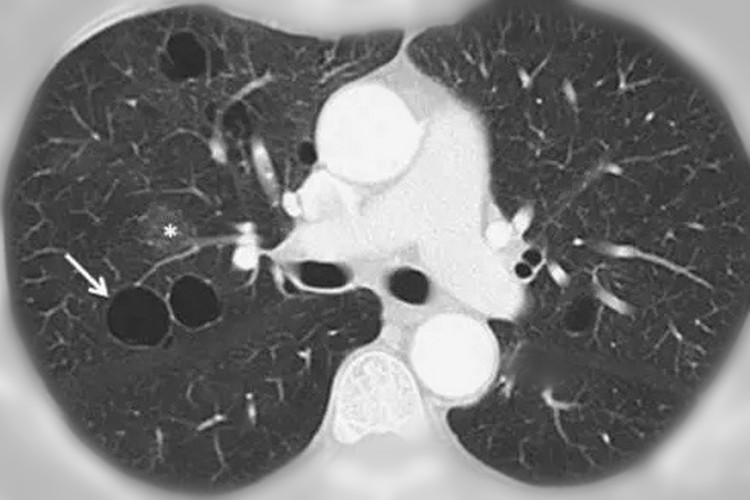

我们的肺是由很多的肺泡构成的, 这些肺泡和蜂窝上的蜂室有点类似,都是基本的组成单位。 这些肺泡是很小的,即便做胸部CT也是看不到的,但是如果在某种原因的作用下,肺泡腔的压力增高,那肺泡内壁就会破裂。

破裂的肺泡会相互融合,这样的话就会形成比原来肺泡更大的囊腔,也就是我们说的肺大疱。 不过需要注意,肺大疱的直径一般来说是大于1cm的,而且里面还含有一些气体。

说白了,肺大疱就是一种含有气体的空腔,较小的单个肺大疱一般来说都没有明显的症状。 体积较大或者多个肺大疱就有可能会出现胸闷、气短等的症状。